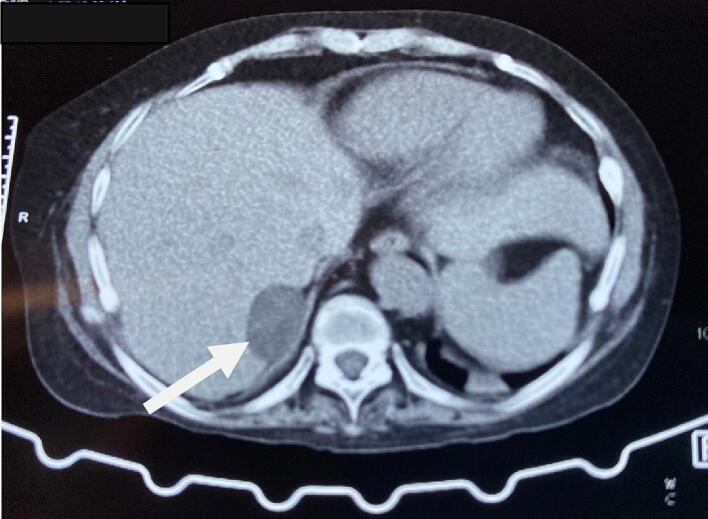

Thus, the patient was initially diagnosed and managed as a case of Cushing syndrome and Pheochromocytoma with resistant hypertension, hypokalemia, Diabetes Mellitus, and hypothyroidism. She was prescribed with Angiotensin receptor blocker, Calcium Channel Blocker, alpha-blocker (Prazosin), spironolactone, potassium chloride, and Insulin. The Computed Tomography (CT) scan of the abdomen revealed a well-defined soft tissue lesion in the right adrenal gland's lateral limb with a high washout likely lipid-poor adenoma (Fig. 1). The visualized spine had diffuse osteopenia with anterior wedging of the D8, D9, D10, D12, and L1 and L4 vertebral bodies. Contrast-enhanced CT (CECT) showed a 3.4 × 2.2 cm enhancing solid cystic lesion abutting the right adrenal gland and segment IV of the liver (Fig. 2).

Fig. 1.

CT abdomen showing well-defined soft tissue lesion in the right adrenal gland (arrow).